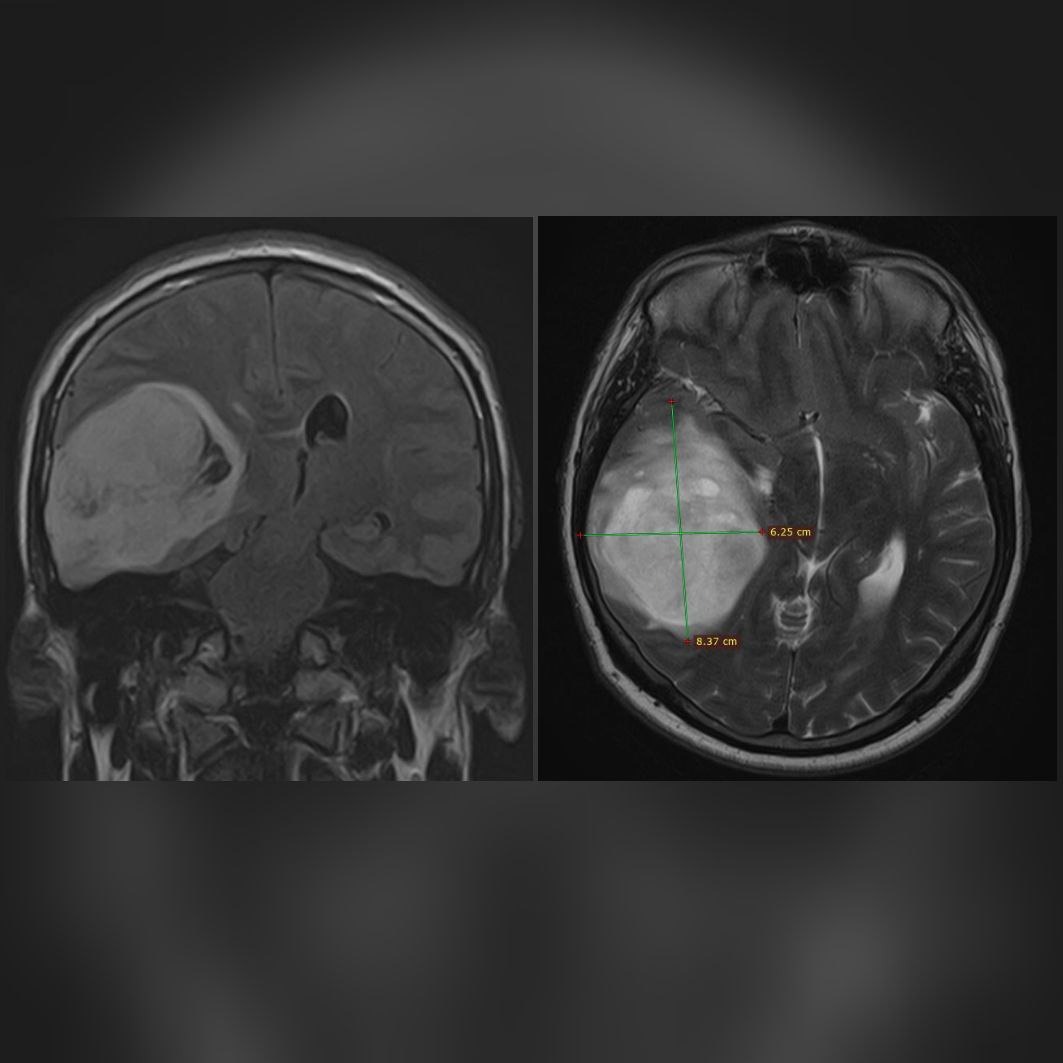

Нейрохирурги ФГБУ «Новосибирский научно-исследовательский институт травматологии и ортопедии им. Я.Л. Цивьяна» Министерства здравоохранения РФ прооперировали мужчину с новообразованием головного мозга.

По результатам МРТ было выявлено новообразование в теменно-височной области головного мозга, тогда Алексей обратился к специалистам нейрохирургического отделения №1 Новосибирского НИИТО им. Я.Л. Цивьяна.

«Что больше всего насторожило — размеры образования и жалобы пациента никак между собой не коррелируются. Возможно, за счёт молодого возраста болезнь протекала бессимптомно, за исключением эпизодических головных болей», — отметил врач-нейрохирург НИИТО, кандидат медицинских наук Игорь Васильев.

Мужчину дообследовали. Образование размером 8 × 6 × 5,5 см оказалась злокачественным, пациенту однозначно было показано оперативное вмешательство.

Нейрохирурги Игорь Васильев и Иван Копылов удалили опухоль. По словам пациента, после операции его состояние значительно улучшилось. Головные боли прошли, кроме того, Алексей перестал заикаться, хотя эта проблема беспокоила его с детства. Теперь мужчину ждет проведение лучевой и химиотерапии.